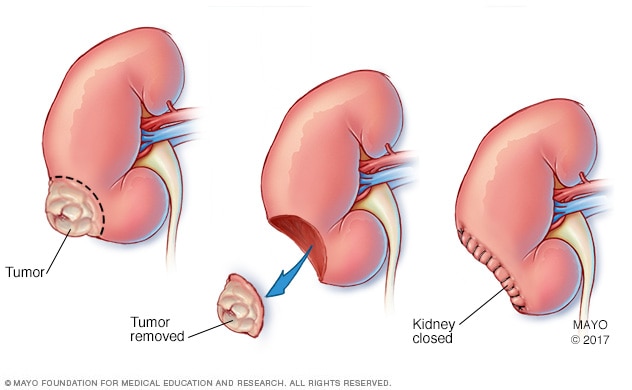

Partial nephrectomy

During a partial nephrectomy, only the cancerous tumor or diseased tissue is removed (center), leaving in place as much healthy kidney tissue as possible. Partial nephrectomy is also called kidney-sparing surgery.

Removing the cancer from the kidney. A partial nephrectomy involves removing the cancer and a small margin of healthy tissue that surrounds it rather than the entire kidney. This procedure also is called kidney-sparing or nephron-sparing surgery. It can be done as an open procedure, laparoscopically or with robotic assistance.

Kidney-sparing surgery is a common treatment for small kidney cancers and it may be an option if you have only one kidney. When possible, kidney-sparing surgery is generally preferred over a complete nephrectomy to preserve kidney function. It also may reduce the risk of later complications, such as kidney disease and the need for dialysis.